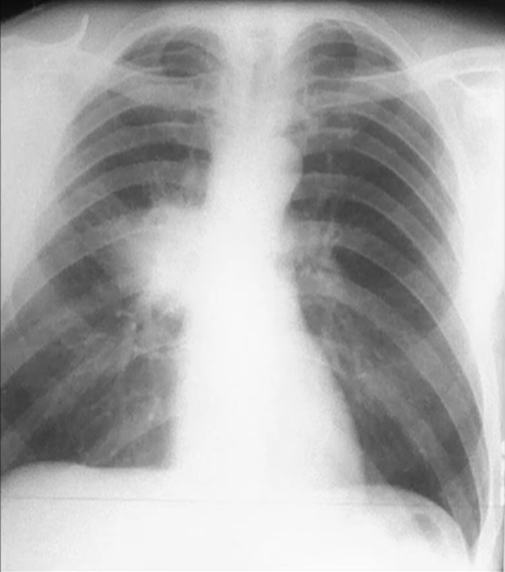

Rx toracică, incidență P-A

DESCRIERE:

în 1/2 sup. a hemitoracelui drept → opacitate triunghiulară cu vf. la hil și baza la periferie, intensitate mare, omogenă

limita spre scizură este netă

fără caracter retractil

bronhograma aerică prezentă (hipertransparențe canaliculare)

DX: pneumonie lobară de lob sup. drept

DD:

atelectazie - caract. retractil

infarct pulmonar